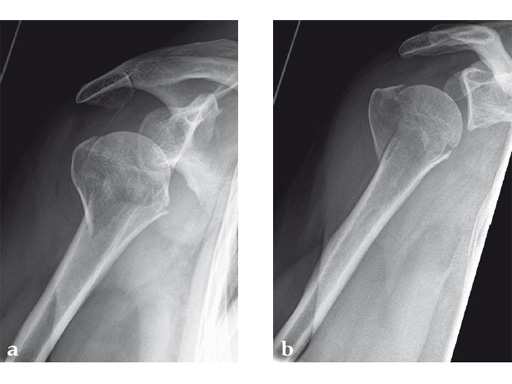

Case 1: A three-part valgus impacted fracture of the proximal humerus in a 47-year-old woman.

Case provided by Stefaan Nijs, Leuven, Belgium